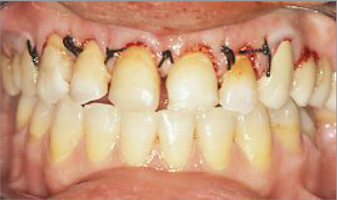

Rehabilitación completa, fundas de porcelana y tratamiento periodontal